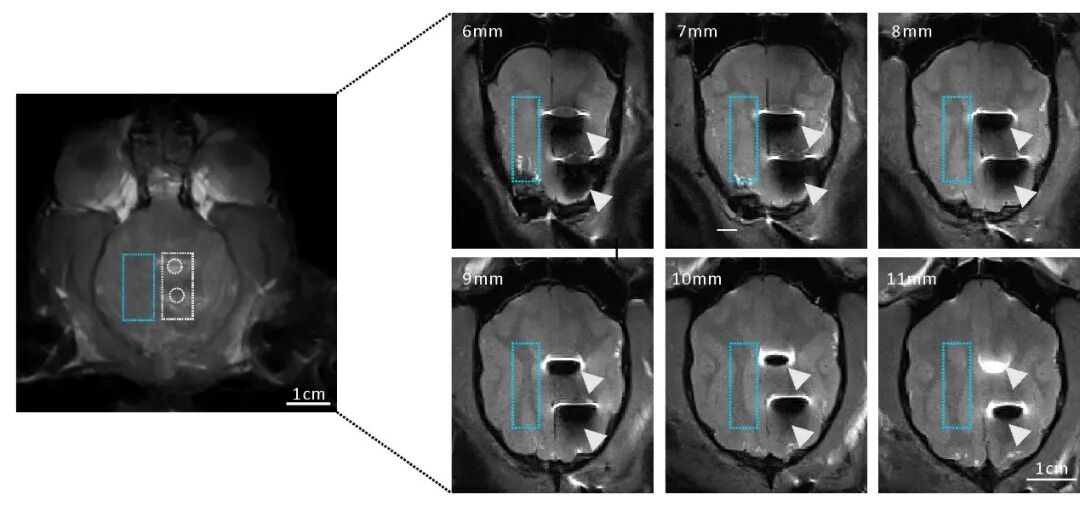

图五:水凝胶皮层电极不影响MRI成像(不会像右方的金属电极产生很大的伪影)

最后基于PVA-ACSF水凝胶的化学构成和脑组织高度相似性,显示水凝胶电极不影响MRI核磁成像。综上这种新型的PVA-ACSF水凝胶电极不仅有巨大的临床应用潜力,它的高度透光性以及核磁兼容性等特点使它可以和光学成像,核磁成像以及光遗传学等先进技术相配合,为基础研究提供更多的选择与可能性。本文的第一作者为浙江大学医学院博士后王晓萌,共同第一作者为浙江大学医学院博士生王梦琪和哈佛大学博士生盛昊。浙江大学生仪学院博士生朱亮为本文做出了重要贡献。浙江大学医学院教授汪浩、浙江大学系统神经与认知科学研究所奚望副研究员以及哈佛大学锁志刚教授为本文的共同通讯作者。原文链接 https://doi.org/10.1016/j.biomaterials.2021.121352